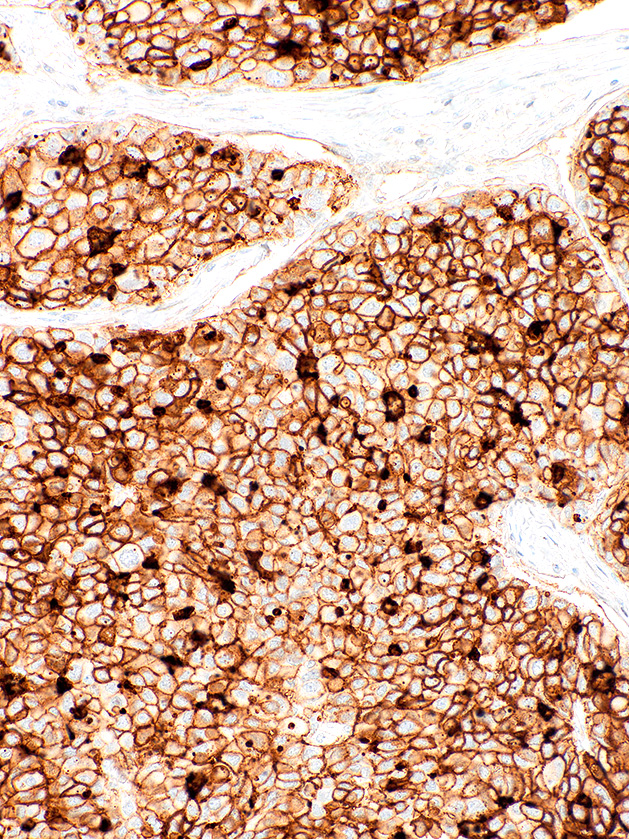

[Genomeme] CD73

CAT. NO. IHC073-100

Cluster of Differentiation 73 (CD73), also known as Ecto-5'-Nucleotidase (ecto-5'-NT), is a cell surface enzyme found in most tissues. CD73 catalyzes the breakdown of AMP to adenosine, thereby modulating inflammatory and T-cell responses. Reports have implicated CD73 expression in tumour progression and carcinogenesis, as CD73 is a key regulatory molecule in the proliferation, migration, and invasion of cancer cells in vitro, as well as tumour angiogenesis and tumour immune escape in vivo. Due to this key involvement in cancer, CD73 has become an appealing target for cancer immunotherapy. CD73 expression has also been linked to favourable prognosis in breast carcinoma.